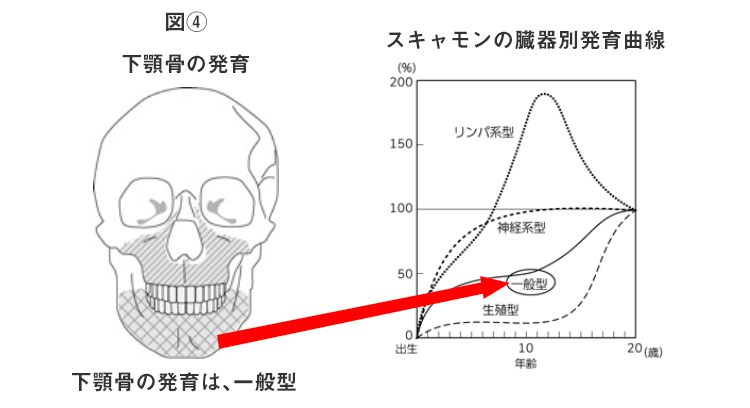

図④で示すように、上顎骨の発育は16歳前で終了しますが下顎骨の発育は、20歳前後まで継続します。つまり、歯列(歯並び)が改善しても、20歳頃までは不安定な時期が続くのです。